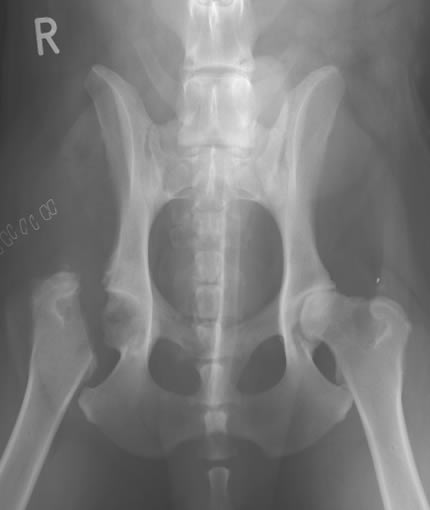

Диагноз ставится врачом-ортопедом, на основании клинической картины, данных анамнеза и рентгенографического исследования.

Болезнь Пертеса у собак следует отличать от других заболеваний со схожими внешними симптомами - вывихом коленной чашечки, дисплазии тазобедренного сустава.